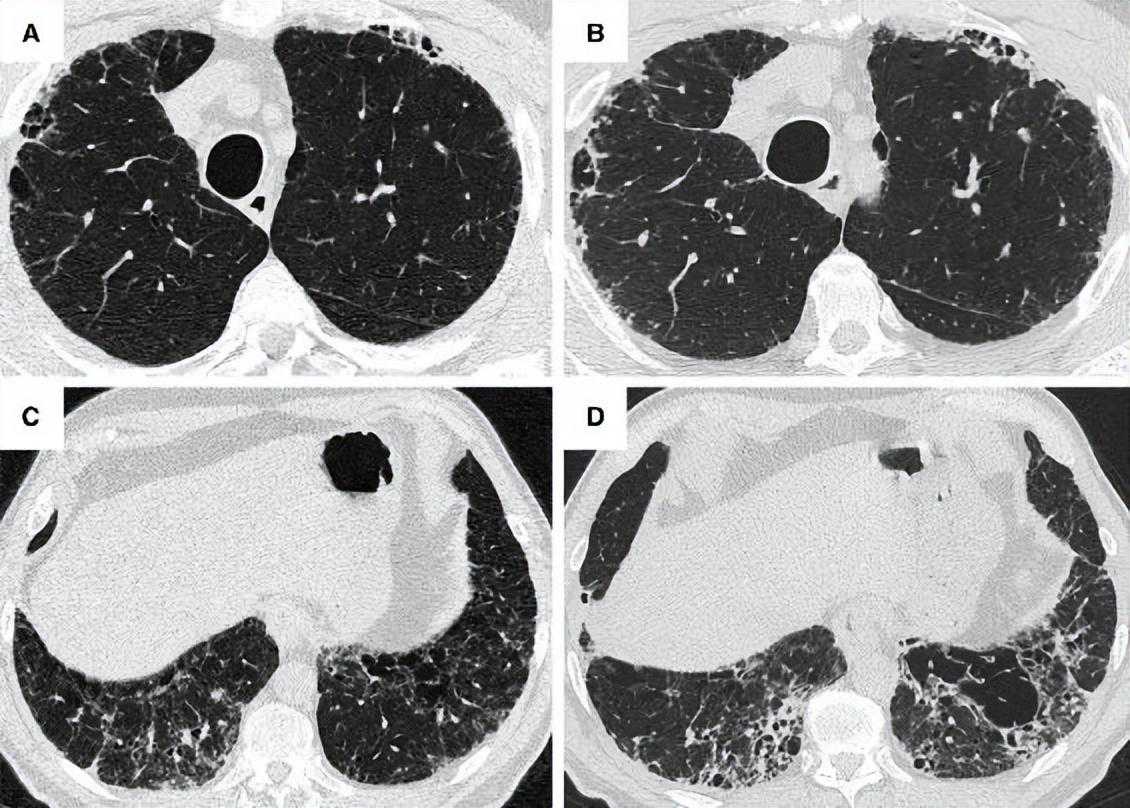

图7:一名66岁男性吸烟者被诊断为特发性肺纤维化和肺气肿(CPFE,大的厚壁囊肿模式),病程4年。在左上角图像中,与肺气肿一致的无清晰可见壁的低密度病变(箭头)在隔膜附近可见,位于肺纤维化区域内。在接下来的4年里,随着纤维化的成熟,低密度病变合并并扩大(箭头),形成厚壁的囊性病变。

图8:69岁男性特发性肺纤维化,HRCT显示双肺弥漫性肺气肿和下肺明显纤维化(CPFE,无法分类模式)。右上肺肺气肿是混合性肺气肿(黑色箭头)和孤立性肺气肿(白色箭头)的组合。中间可见混合性肺气肿,下部可见混合性和孤立性的肺气肿和小叶中央肺气肿。

适当评估ILD的HRCT扫描参数可以在其他地方找到[144]。当肺气肿和纤维化在空间上重叠时,经典的HRCT模式可能发生改变。例如,小叶间隔伴胶原纤维的扩张可使间隔性肺气肿表现为蜂窝状囊肿。大多数研究集中在IPF患者和/或HRCT为UIP模式的患者[1,24-26,29,30,32,33,33,38,55,56,58,56,61,120,121,137,138,141,145-153],尽管其他研究也包括了各种ILD亚型和成像模式的患者。鉴于CPFE患者在HRCT上有UIP模式的比例很高(表E3)[1,137,145-147],区分混合性肺气肿与蜂窝状囊肿存在具有挑战性。肺气肿和纤维化的共存也可以形成一种厚壁囊性病变的成像模式[141,142],这被认为反映了肺气肿的扩张,因为被相邻收缩的纤维化肺拉开。委员会建议,这个过程可以被称为牵引性肺气肿,因为它假定的机制类似于在纤维化区域常见的牵拉性细支气管扩张。厚壁囊性病变主要位于肺后基底区,由网状阴影包围的大肺气肿区组成,在CPFE中比在单独IPF中更常见[141,142]。然而,尚不清楚厚壁囊性病变是否是CPFE的特异性病变,其演变过程尚未得到充分描述。